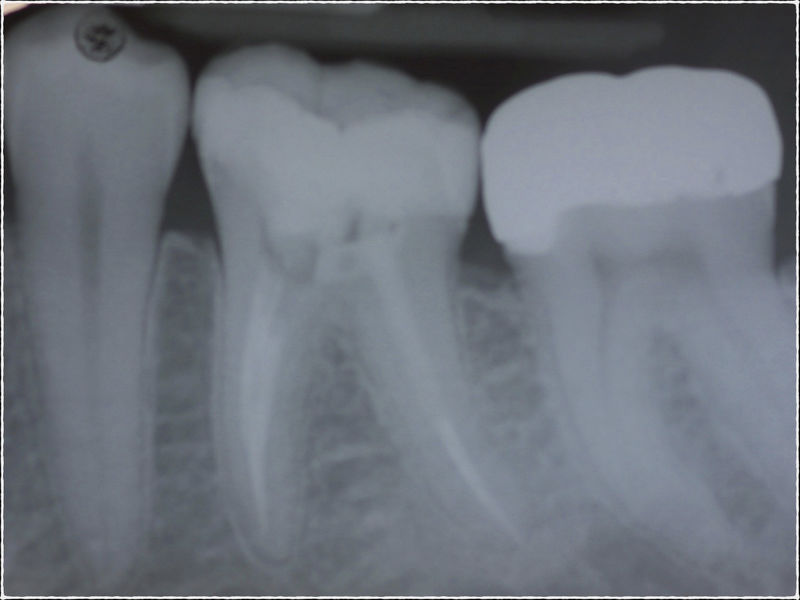

Disciplina fundamental de la Odontología enfocada en el diagnóstico, prevención y tratamiento restaurador de las piezas dentales que han sufrido daños. Su objetivo principal es devolver al diente su equilibrio biológico, funcional y estético cuando su integridad ha sido alterada. Resinas directas, incrustaciones, coronas.

La restauración de un diente tras una endodoncia, es crucial para su supervivencia a largo plazo, ya que el procedimiento puede debilitar la estructura dental. El tipo de restauración elegido depende principalmente de la cantidad de estructura dental remanente después de la endodoncia. Principalmente se usan incrustaciones, coronas y/o postes.